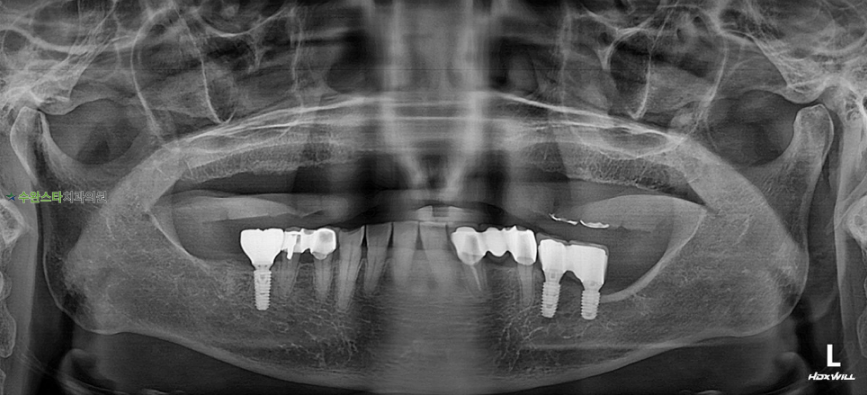

내원 시 파노라마

처음 내원 시 파노라마, 70대 여성 (2025. 12촬영)

내원 시 파노라마 사진입니다.

치료 기간 동안 환자분의

불편함을 최소화하기 위해

상악동 거상술 + 뼈 이식 + 상악 임플란트를

한 번의 수술로 진행하기로 하였습니다.